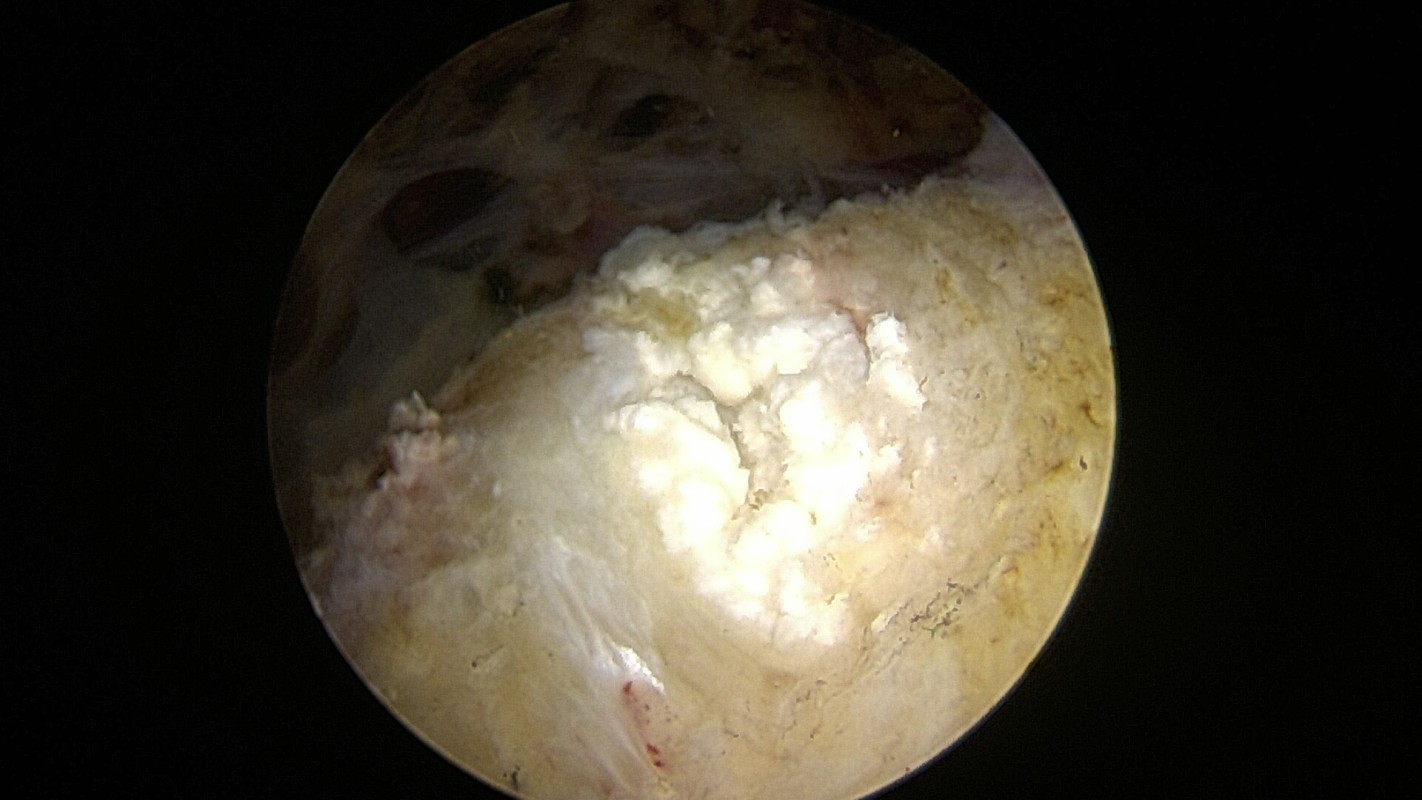

Absence totale de tendon sus épineux